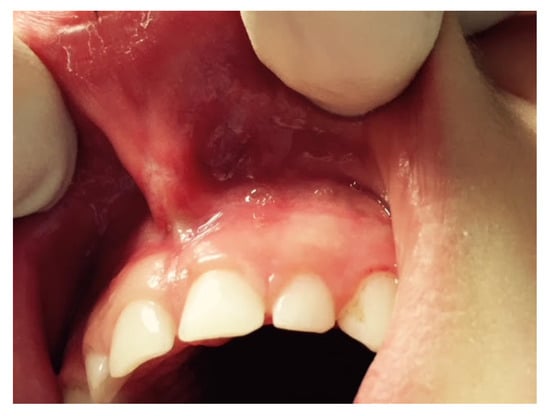

Furthermore, the diode laser has become highly popular in dental practice given its small size, low cost and easy application for minor soft tissue surgery, for its properties of straightforward tissue incision, and its coagulation and post-surgery benefits [26,27] (Figure 7).

Figure 7.

Labial frenulum treated by laser frenectomy after healing.